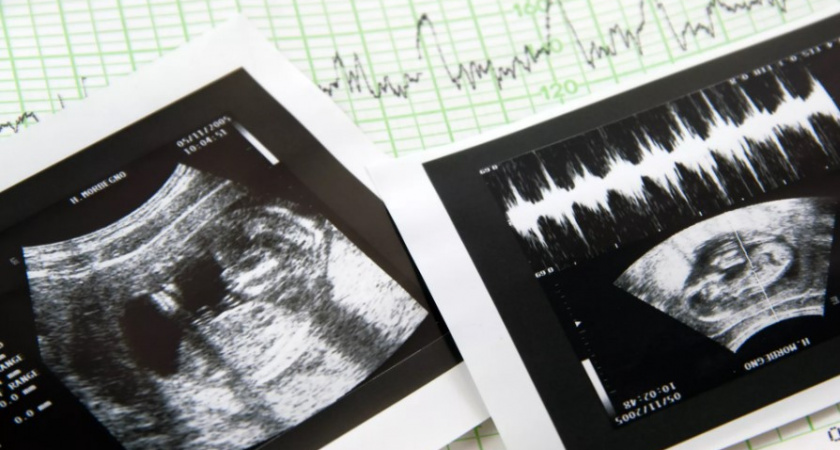

Ирина Волынец, представитель по правам ребенка в Татарстане, предложила ввести премию для медицинских работников, которые помогли женщине отказаться от аборта, считая это эффективным способом увеличения рождаемости в России. Она также предложила финансировать эту премию из средств, выделяемых на аборты из федерального бюджета, и считает, что это станет мотивацией для медицинских работников сохранять жизнь нерожденных детей.